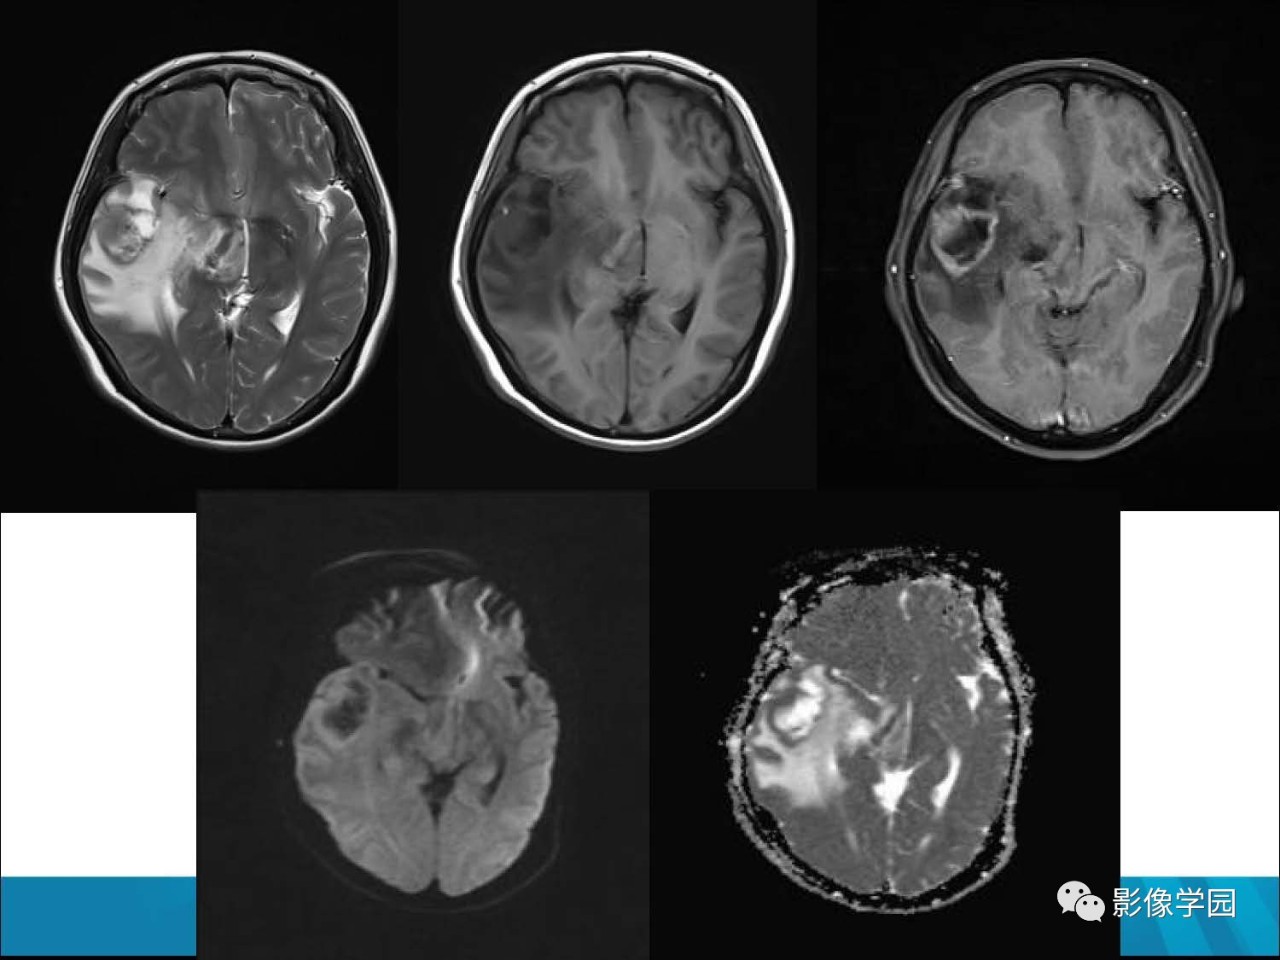

颅内环形强化病变的诊断思路

颅内环形强化病变的诊断思路中南大学湘雅二医院